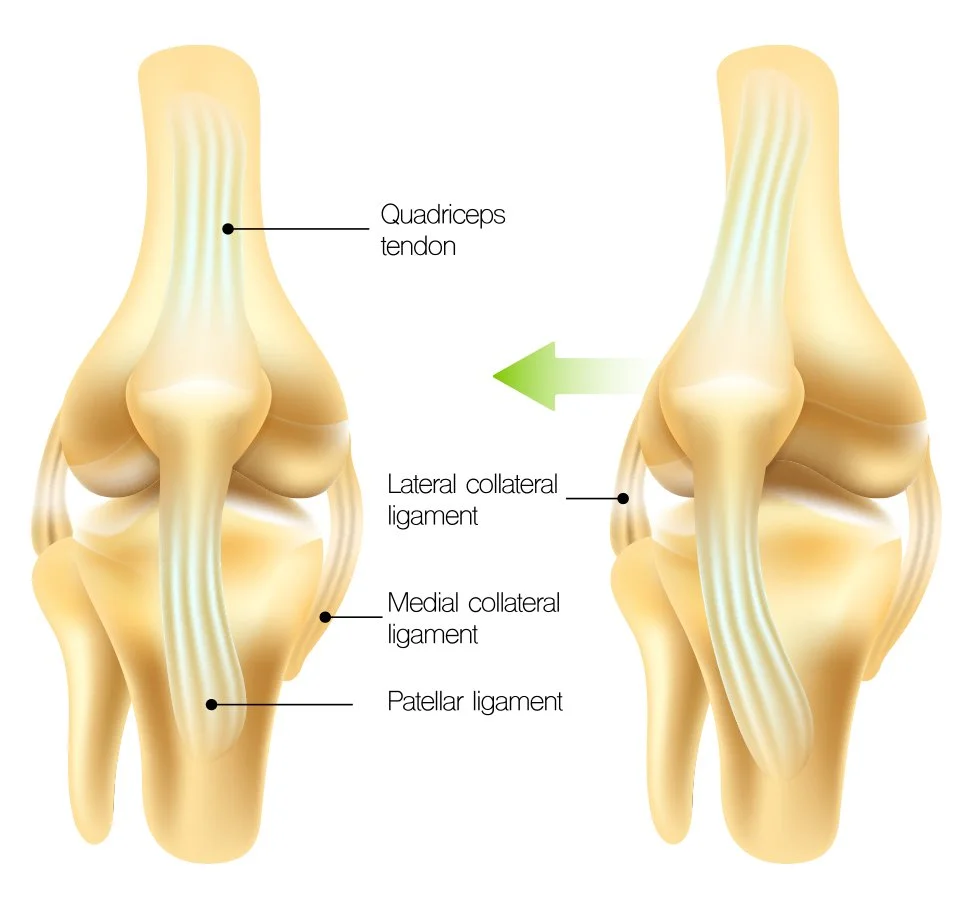

The patella (kneecap) normally sits within a groove at the end of the femur (the trochlea) and glides smoothly when you bend and straighten your knee. Certain factors—such as trauma, ligament injury, or anatomical variations—can cause the patella to slip out of place (dislocate) or feel unstable, particularly during twisting, kneeling, or pivoting activities.

• The MPFL is the main soft-tissue stabiliser preventing the kneecap from slipping sideways.

• If torn or stretched, it can be reconstructed using a tendon graft, typically taken from the hamstring.

• Bone tunnels are drilled in the patella and femur, and the graft is fixed with screws or anchors.

• X-rays are used during surgery to ensure correct graft placement.

• This is the most common procedure performed for recurrent patella dislocations.